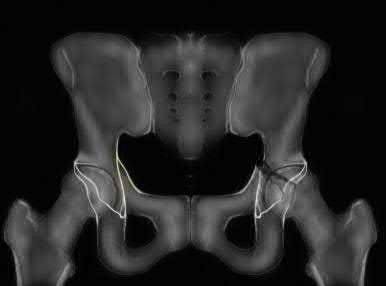

Question 1

A 12-year-old obese boy presents with vague left thigh and knee pain. He is diagnosed with a Slipped Capital Femoral Epiphysis (SCFE) as seen in similar clinical scenarios.

During percutaneous in-situ fixation, unrecognized penetration of the guide wire into the hip joint occurs. What is the most likely specific complication resulting from this technical error?

Explanation

Chondrolysis is a severe complication of SCFE characterized by rapid destruction of the articular cartilage. While it can occur idiopathically, its most established iatrogenic cause is unrecognized intra-articular hardware penetration. The 'approach-withdraw' fluoroscopic technique is required during pinning to assure pins are entirely intraosseous. Avascular necrosis (AVN) is usually due to damage to the epiphyseal blood supply (retinacular vessels) secondary to the initial displacement, forceful closed reduction, or posterosuperior pin placement.